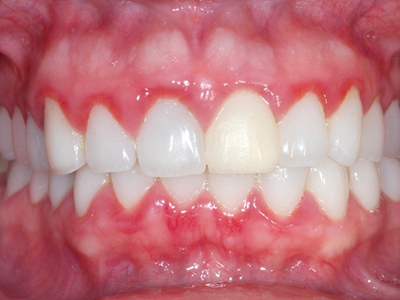

牙龈炎是发生于牙龈组织的炎症,患者可出现牙龈出血伴肿胀、发红、正常形态改变和偶尔不适等症状。本病主要由口腔卫生状况差导致,包括口腔不洁、牙菌斑等,诊断依据临床检查,治疗包括专业牙齿清洁和加强家庭口腔卫生。

牙龈炎可先引起牙齿与牙龈之间的沟(龈沟)加深,然后牙龈充血,炎症围绕一个或多个牙齿,伴牙龈乳头肿胀和易出血。一般无痛,可自行消退,也可维持轻度炎症数年。